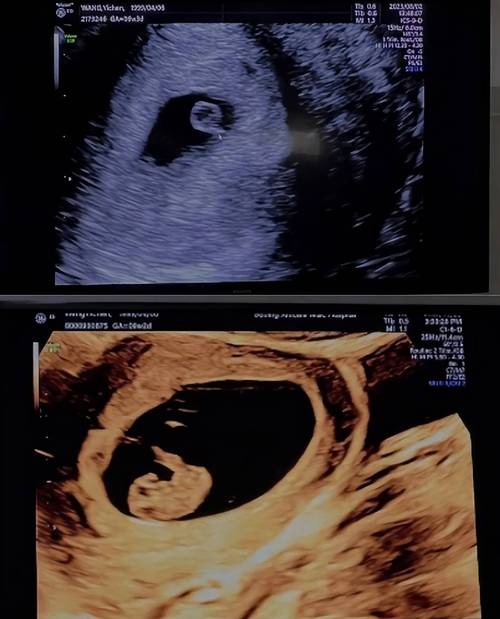

- 确认怀孕和孕周:孕早期通过B超可以确认是否为宫内妊娠,排除宫外孕的危险,并测量胎芽大小来核对孕周。

- 监测胎儿生长发育:定期测量胎儿的双顶径、头围、腹围、股骨长等,评估胎儿生长发育是否在正常范围内。

- 筛查胎儿结构畸形:这是中孕期B超(通常在孕20-24周)最重要的任务,俗称“大排畸”,可以筛查出大部分严重的先天性结构异常。

| 孕早期 (6-8周) | 确认宫内妊娠,排除宫外孕。 看到胎心胎芽,确认胚胎存活。 核对孕周(如果末次月经不规律)。 |

| 孕中期 (11-13+6周) | NT检查(颈项透明层厚度测量),结合早期唐氏筛查,评估胎儿染色体异常的风险。 |

| 孕中期 (20-24周) | 大排畸B超,系统筛查胎儿的各个器官是否存在结构畸形,这是最重要的一次B超。 |